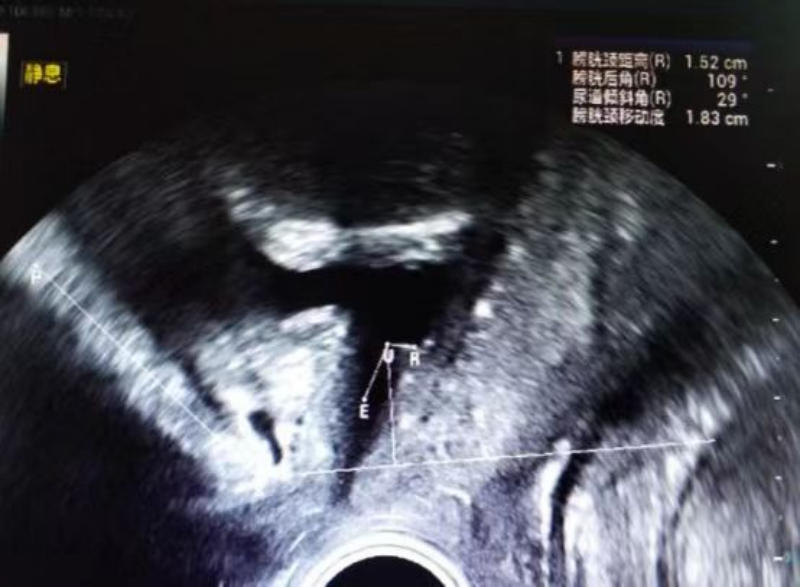

以往盆底检查主要依靠MRI检查,但费用高,时间长,无法动态观察女性盆底功能,而盆底超声检查以其无创性、可重复性、无辐射、费用低廉等优点被广泛用于盆底功能障碍性疾病的诊断和治疗后的疗效评估。目前,超声是诊断盆底功能障碍性疾病首选影像学检查方法 ,盆底四维超声已广泛应用于临床。

2.指导患者正确的完成缩肛及Valsalva动作,实时动态观察盆底脏器位置及功能;

2.仔细听从医生的指令做缩肛和用力动作(Valsalva动作),医生会在静息、缩肛、用力时分别测量相关数据进行评估。